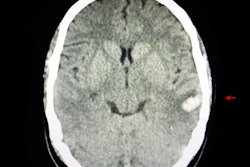

The software, called BioMind AI, correctly diagnosed brain tumors in 87% of 225 cases in about 15 minutes. A team of senior doctors, however, could only manage 66% accuracy, China.org.cn reported. In addition, the software correctly predicted brain hematoma expansion in 83% of cases, compared with 63% accuracy by the physicians.

BioMind AI was developed by the Artificial Intelligence Research Centre for Neurological Disorders at Beijing Tiantan Hospital and a research team from Capital Medical University. It was trained using tens of thousands of nervous system-related diseases archived by Tiantan Hospital over the past 10 years, and it can diagnose common neurological diseases such as meningioma and glioma with an accuracy rate of more than 90%, according to the article.